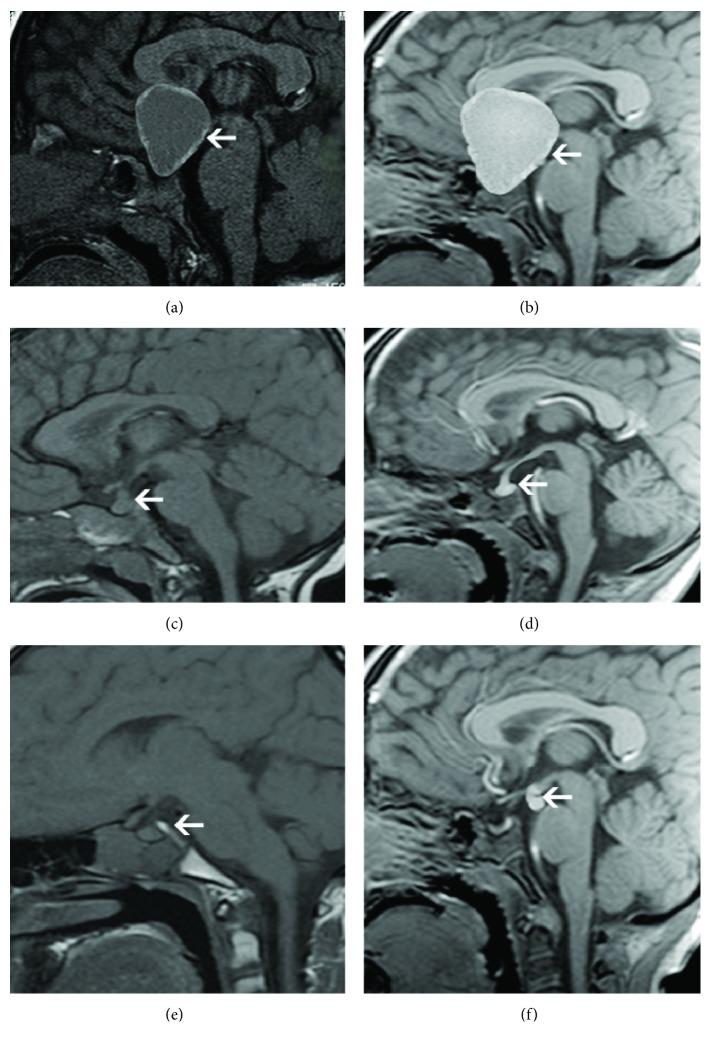

Seventy-nine patients with CDI (CDI group) hospitalized from July 2012 to March 2017 and 43 healthy children (control group) were enrolled in this study. All cases underwent MRI examination including T1-weighted three-dimensional magnetization-prepared rapid gradient-echo (T1WI-3D-MP RAGE) imaging sequences. The pituitary volume, the signal intensity of posterior pituitary, and the morphology of pituitary stalk were measured between two groups. The medical history, urine testing, imaging of hypothalamic-pituitary region, and hormone levels were also recorded.

Age and gender were matched between the CDI and control groups. The height and BMI in the CDI group were less and the urine volume in 24 h was higher than those in the control group. The signal intensity of the posterior pituitary was higher in the control group, whereas the pituitary volume was smaller in the CDI group. In the CDI group, 44 cases presented with morphological changes of the pituitary stalk. Clinical symptoms mainly included polydipsia, polyuria, short stature, and vomiting. All patients were confirmed by water deprivation vasopressin test. Forty-four CDI children were associated with hypopituitarism, including 33 cases of PSIS with multiple pituitary hormone deficiencies (MPHD) and 11 cases of growth hormone deficiency (IGHD). The pituitary volume in the cases of pituitary stalk interruption syndrome (PSIS) with MPHD was smaller than that in the IGHD patients.

The signal intensity ratio of the posterior lobe, pituitary volume, and the morphology of pituitary stalk on T1WI-3D-MP RAGE image contribute to the diagnosis of CDI.